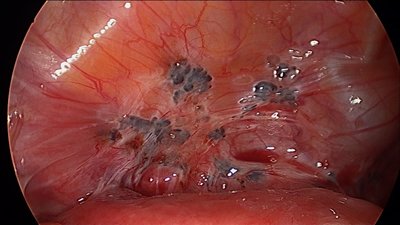

Lo más sorprendente es que la enfermedad está considerada como benigna y por tanto son casi inexistentes los programas de investigación y especialización sobre esta patología. Entre sus consecuencias más graves están los problemas de infertilidad. Si la enfermedad se complica puede suponer la pérdida de órganos reproductores, riñones, parte del colon, hígado o incluso verse dañado el pulmón, el corazón y el cerebro. En ocasiones la única solución que nos dan es medicarnos a base de hormonas como si de una cura se tratase, y en los casos más severos, cuando un órgano vital se afectado hay que recurrir a intervención quirúrgica por laparoscopia.

Most surprising is that the disease is considered benign and therefore almost no research programs exist and there are no doctors specializing on this pathology. Among its most serious consequences are infertility problems. If complications arise it can mean the loss of reproductive organs, kidneys, part of the colon, liver or even damaged veins, lungs, heart and brain. Hormone therapy is the only treatment and the only solution that is given to us in order to treat the disease, and it is pitched like it will be the cure, but it isn't. And in the most serious cases, when a vital organ has been affected, surgery by laparoscopy is necessary.